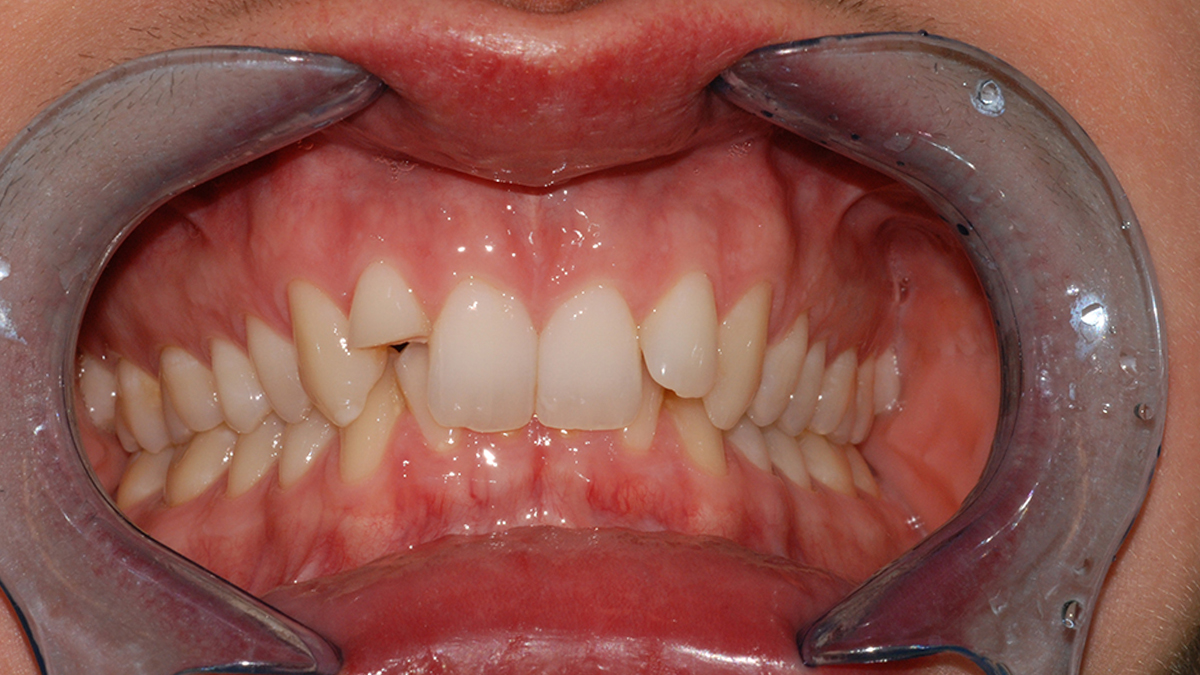

Sajnos a nem megfelelő szájhigiénia és-vagy nem megfelelő táplálkozás fogszuvasodás kialakulásához vezethet. Ennek terápiája a fertőzött, szuvas foganyag eltávolításával, majd a fog tömőanyaggal vagy betéttel való helyreállításával lehetséges.

Általában ha a fognak csak egy kisebb része szuvas, a hiányzó rész kitisztítás után tömőanyaggal pótolható. A töméskészítést helyi érzéstelenítésben végezzük, egy alkalmat vesz igénybe. A tömőanyag egy speciális műanyag, kompozit, amely mind színében, mind fizikai tulajdonságaiban nagymértékben hasonlít a természetes foghoz, ezért alkalmas tartós és esztétikus tömések készítésére. Töméskészítés során a gyurmaszerű anyagot kis adagokban helyezzük az üregbe, majd az egyes rétegeket speciális lámpával világítjuk meg, melynek hatására megszilárdulnak. A tömés elkészültével az anyag kötése befejeződik, a fog terhelhető.